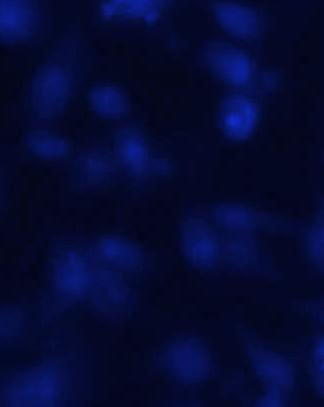

Hoescht staining

The U-87 MG Cells were treated by GCB loaded with MPEG-PCL nanoformulation (GCBNP 3) which shows maximum intracellular accumulation. The cellular uptake of GCB loaded MPEG-PCL nanoparticles in U-87 MG cells were examined under fluorescence microscopy and the images are shown in fig.11.

The results showed significant apoptotic cell death in GCB loaded MPPEGPCL nanoformulation compared with the pure drug. This indicates that the nanoformulation penetrates the cell membrane of glial cells.

Fig. 11: Comparison of penetration of control, pure drug, PNP and GCBNP 3 in U-87 MG cell lines using Hoechst 33342 DNA staining technique